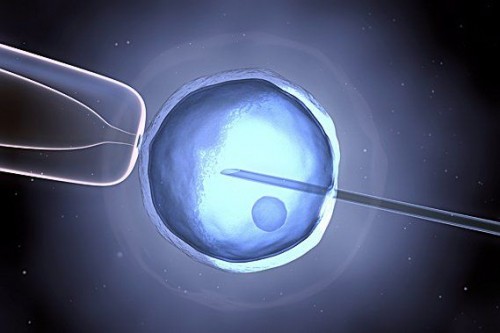

Fecondazione assistita, stress fa male. Per questo le prof…